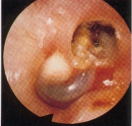

真珠腫性中耳炎

鼓膜の内側の中耳に皮膚の一部が入り込み、そこで皮膚からの落屑物が蓄積し、炎症を起こすことで耳の骨を壊していく病気です。